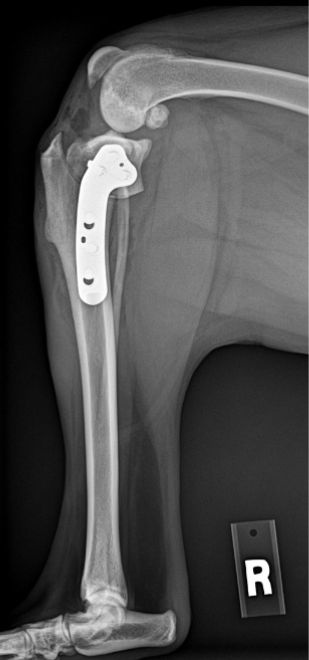

ADVANCED VETERINARY ORTHOPEDIC SERVICES

Our world-class, board-certified veterinary surgeons are dedicated to providing the most advanced canine orthopedic veterinary surgery and musculoskeletal assessment to ensure your beloved pet receives the most appropriate and comprehensive veterinary treatment available.